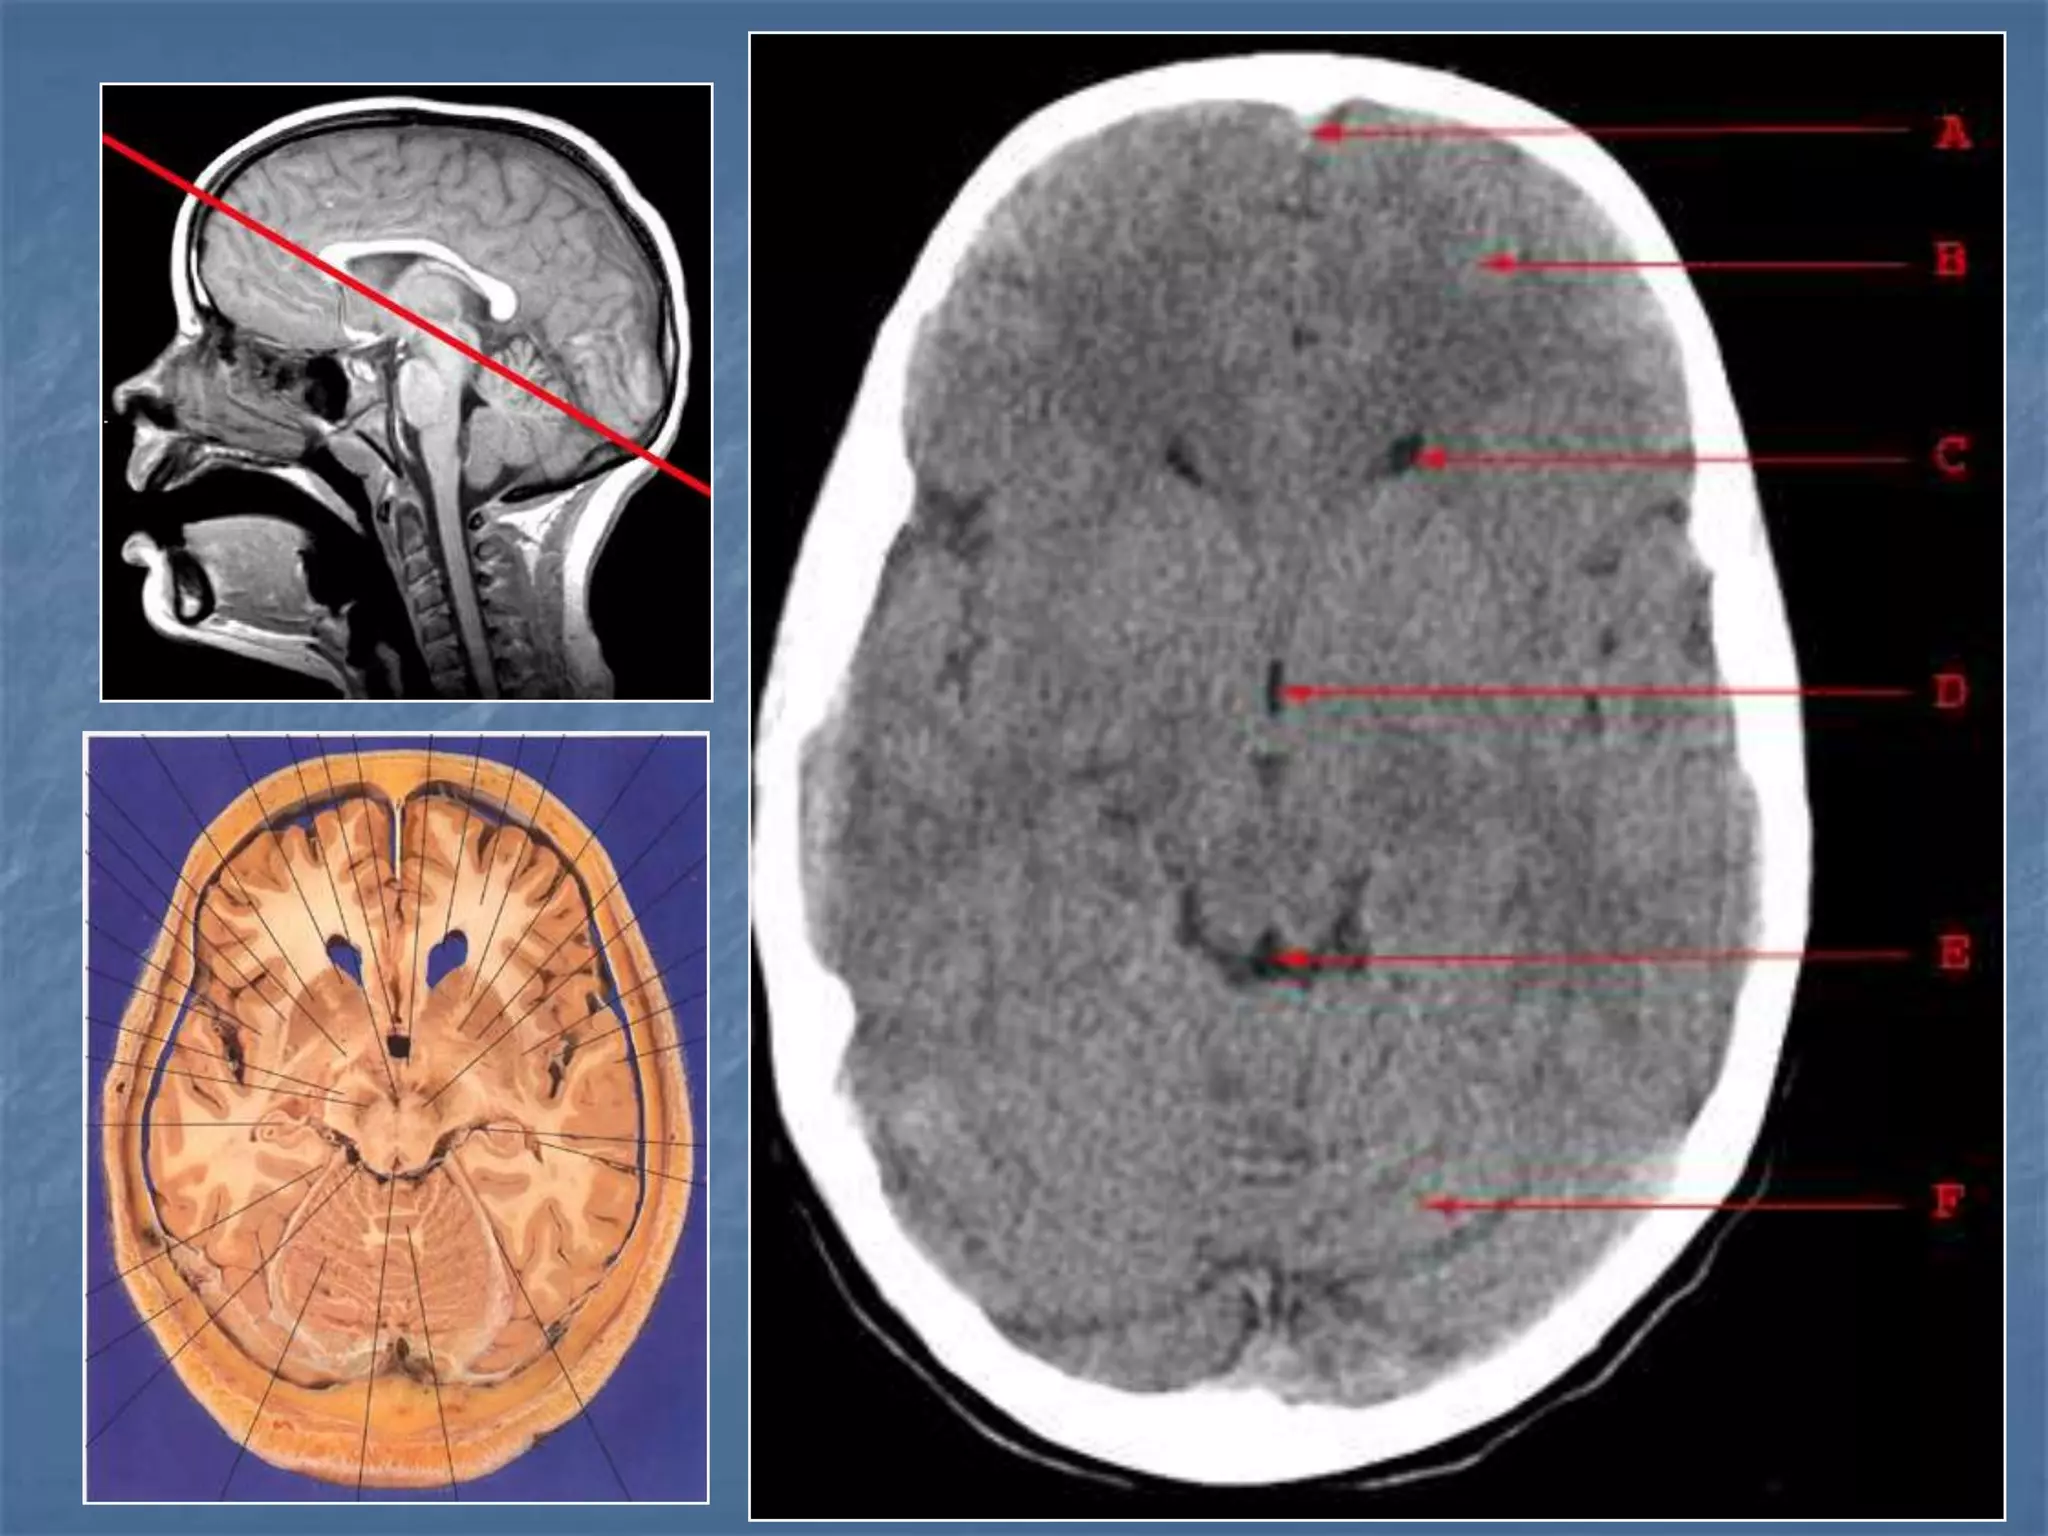

How the CT study is usually planned…

15-20 degree

angulation to

canthomeatal line

to decrease

radiation to the

lens.

 Thinner sections

are studied

through the

posterior fossa

Hounsfield Units

AIR - - 1000

FAT - - 30 to -100

CSF - 0

GREY MATTER - 32 - 41

WHITE MATTER - 23 - 34

ACUTE BLOOD - 56 - 76

CALCIFICATION - 60 - 400

BONE - 1000